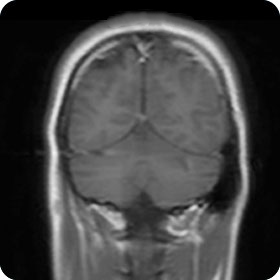

Schädel

| CT | Stroke mit Perfusion/Angiographie, Trauma, Blutung, knöcherne Pathologien inkl. Felsenbein, Mittelohr, NNH |

| MRI | Infarkt, vaskuläre Pathologien, demyelinisierende Erkrankungen, Entzündung, Schwindelabklärung, Diagnostik von Sehstörungen, Epilepsie-/Demenz-Abklärung |